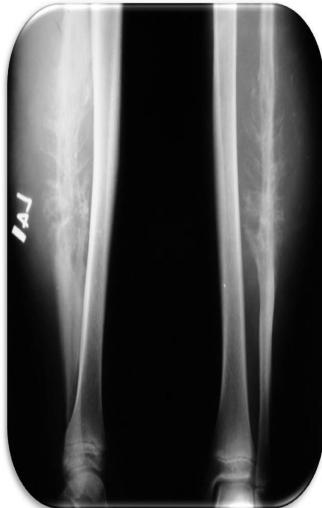

Diaphyseal Lesions: Detailed Examples

Common Diaphyseal Tumors

- Osteoid osteoma

- Fibrous dysplasia

- Osteofibrous dysplasia

- Adamantinoma

- Ewing’s sarcoma

Osteoid Osteoma

Thick cortex

Other Diaphyseal Lesions

Could be malignant, even though no periosteal reaction, may be due old fracture

Pathological fracture, after metastasis